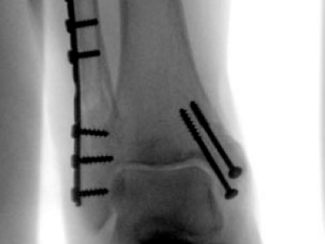

Internal Fixation

Internal fixation involves the surgical placement of screws, plates, rods, or wires directly onto or within the bone to stabilize the fracture. This technique is often used for more severe fractures, such as displaced or unstable fractures.

Internal fixation refers to the method of physically reconnecting the bones. This might involve special screws, plates, rods, wires, or nails that the surgeon places inside the bones to fix them in the correct place. This prevents the bones from healing abnormally. The entire operation usually takes place while you are asleep under general anesthesia.

Screws and plates are used to hold bone fragments together. Plates are attached to the surface of the bone with screws to maintain alignment.